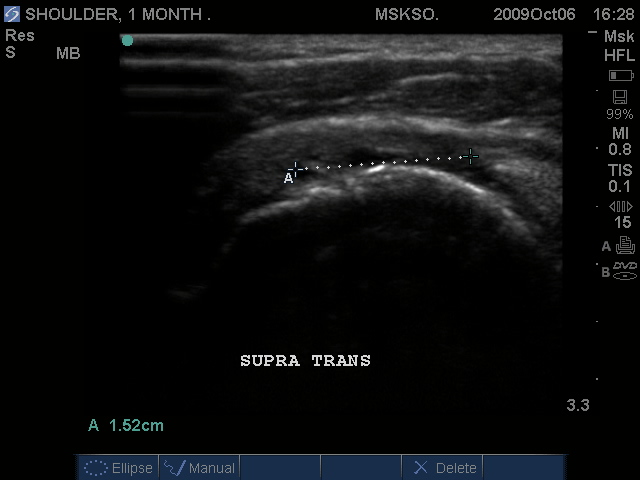

Supraspinatus imaged distally over the Greater Tuberosity. Large articular surface tear measured anterior to posterior, Infraspinatus tendon is seen at the right as a hyperechoic tendon transverse oblique over the posterior humeral head.